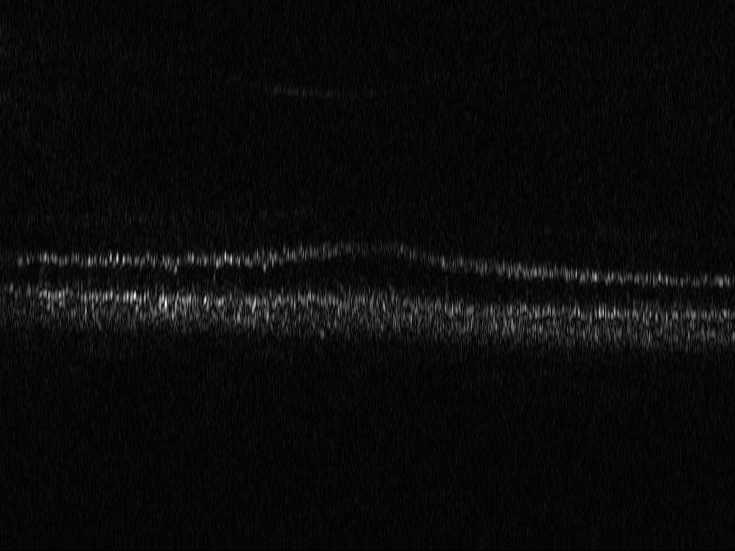

3.4 OCT

Optical coherence tomography (OCT) is a well established imaging technique based on low-coherence interferometry that enables volumetric imaging of biological tissue at high resolution (citep \@BBN(Pircher, 2018)). Light is split into a reference and a sample arm, recombined after being backreflected by a mirror and backscattered at different depths of the sample, in the respective paths. Using Fourier domain OCT (citep \@BBN(Fercher et al., 1995)), a tomographic image of the sample is reconstructed by spectral analysis of the resulting interference patterns. In order to achieve optimal axial resolution (i.e. resolution in depth), it is essential to match dispersion between the two arms of the interferometer (citep \@BBN(Drexler et al., 2008)). This can be achieved on the one hand by carefully matching the length of the arms and the corresponding dispersive materials and on the other hand by numerical methods in the reconstruction process (citep \@BBN(Wojtkowski et al., 2004)). OCT was originally developed for imaging of the retina and, while there are many other applications of OCT available, its highest impact is to this day in ophthalmology, where this technology plays a critical role in correct diagnosis (citep \@BBN(Pircher, 2018)).

3.4.1 Reconstruction problem

Most commonly, OCT processing algorithms compute intensity images from the recorded spectral data. Standard algorithms include a step that performs numerical dispersion compensation. Methods are available which automatically determine the correct dispersion compensation parameter (citep \@BBN(Wojtkowski et al., 2004)), but the stability of automatic numerical dispersion compensation methods under varying imaging conditions is not fully understood. Besides the dispersion parameter, there exist also algorithms that provide geometrical corrections within the reconstruction process, see e.g. (citep \@BBN(Shirazi et al., 2020)), namely the correction of rotation introduced by eye motion and correction of the curvature of the retina. Automatic parameter selection for the geometric corrections is a challenging task which has so far not been addressed and therefore these parameters are usually set manually, which is very time-consuming especially in the case of clinical studies where often a large number of patients and imaging locations is included.

It is important to note that errors in the considered corrections have varying impact on the usability of the resulting intensity data. Errors in the geometrical corrections can be fixed in an additional post-processing step after the reconstruction. An incorrect choice of the dispersion compensation parameter however results in deteriorated axial resolution which cannot be corrected in post-processing. The OCT processing of the spectral data would have to be repeated. Therefore, OCT image data with faulty dispersion compensation should be evaluated as having worse image quality than image data with faulty rotation and curvature compensation. A metric that is able to distinguish between the image quality criteria at hand would be helpful to automatically find the correct parameters of the algorithm in a robust manner.

3.4.2 Data

We use here representative image data obtained using an adaptive optics (AO) supported spectral domain OCT system (citep \@BBN(Brunner et al., 2021)). Cross-sectional images (B-scans) were retrieved from two AO-OCT volumes recorded in a young healthy volunteer (27 years, female, right eye) with a field of view of approximately 4×4superscript4superscript44^{\circ}\times 4^{\circ} (corresponding to  1.4×1.4mm1.41.4𝑚𝑚1.4\times 1.4mm on the retina). Different imaging locations and focus settings were considered. One data set was recorded in the fovea with the focus of the imaging beam set to the posterior retina and one data set close to the optic disc with the focus shifted to the anterior retina. An algorithm including dispersion compensation and geometrical corrections was employed (citep \@BBN(Shirazi et al., 2020)) for the reconstruction. The images are shown on a linear intensity grey scale. The reference images, (a) in Figure 9 and 10, were obtained by manually optimizing over the parameters that define the compensation of dispersion, rotation and curvature, respectively. The examples in Figure 9 and 10 compare the chosen reference to three sub-optimal reconstructions, where (b) had a bad choice for the rotation correction parameter, (c) for the curvature correction parameter and (d) for the dispersion compensation parameter.

Refer to caption

(a) Reference

(b) (26.88, 0.71, 0.05)

(c) (26.84, 0.72, 0.04)

(d) (29.94, 0.77, 0.06)

Figure 9: OCT reference reconstruction (a) and reconstructions with sub-optimal parameters (b)-(d) leading to geometric deviations (b)-(c) and low resolution (d). Here, (d) is wrongly judged as best reconstruction by SSIM and PSNR, LPIPS is able to ignore the small spatial deviations.

(b) (25.20, 0.55, 0.04)

(c) (26.49, 0.66, 0.03)

(d) (27.78, 0.70, 0.06)

Figure 10: OCT reference reconstruction (a) and reconstructions with sub-optimal parameters (b)-(d) leading to geometric deviations (b)-(c) and low resolution (d). Here, (d) is wrongly judged as best reconstruction by PSNR and SSIM, LPIPS is able to ignore the small spatial deviations.

FR-IQA mismatches

Good dispersion compensation should provide images with a depth resolution that is optimized for the system at hand. In the ophthalmic application of AO-OCT, this high axial resolution allows for the visualization and identification of the different retinal layers (citep \@BBN(Shirazi et al., 2020; Brunner et al., 2021; Wojtkowski et al., 2004)), different retinal layers and structures, such as blood vessels. In the first example Figure 9 the clear separation of the different layers in the posterior retina, such as the photoreceptor bands and the retinal pigment epithelium, is crucial for clinicians/researchers who investigate the structure and function of the healthy and the diseased human retina (citep \@BBN(Jonnal et al., 2014)). Therefore, in this example, the reconstruction shown in Figure 2 (d) should have clearly been rated the lowest as the axial resolution is the lowest because of faulty dispersion compensation, which cannot be fixed by further post-processing. In the second example Figure 10, a cross-sectional view of three retinal vessels which are embedded in the nerve fibre layer is given. Changes in the thickness of vessel walls are an important early biomarker for retinal diseases such as diabetic retinopathy, cf. (citep \@BBN(Bakker et al., 2022)). Again, the reconstruction with faulty dispersion compensation shown in Figure 10(d) should have been rated the lowest. The loss in axial resolution worsens the visualisation of the vessel walls and would lead to inaccurate measurements of the vessel wall thickness. In the current version of the algorithm the parameters which determine the amount of dispersion, rotation and curvature compensation applied by the reconstruction algorithm have to be set manually. Therefore, automated evaluation would be very helpful to fasten the process. The standard metrics are not suitable here, as PSNR and SSIM wrongly assess that reconstruction as the best, and, as expected, penalize harder the geometric deviations in (b) and (c). The geometric deviations are not beneficial, but could be fixed by post-processing unlike image (d).